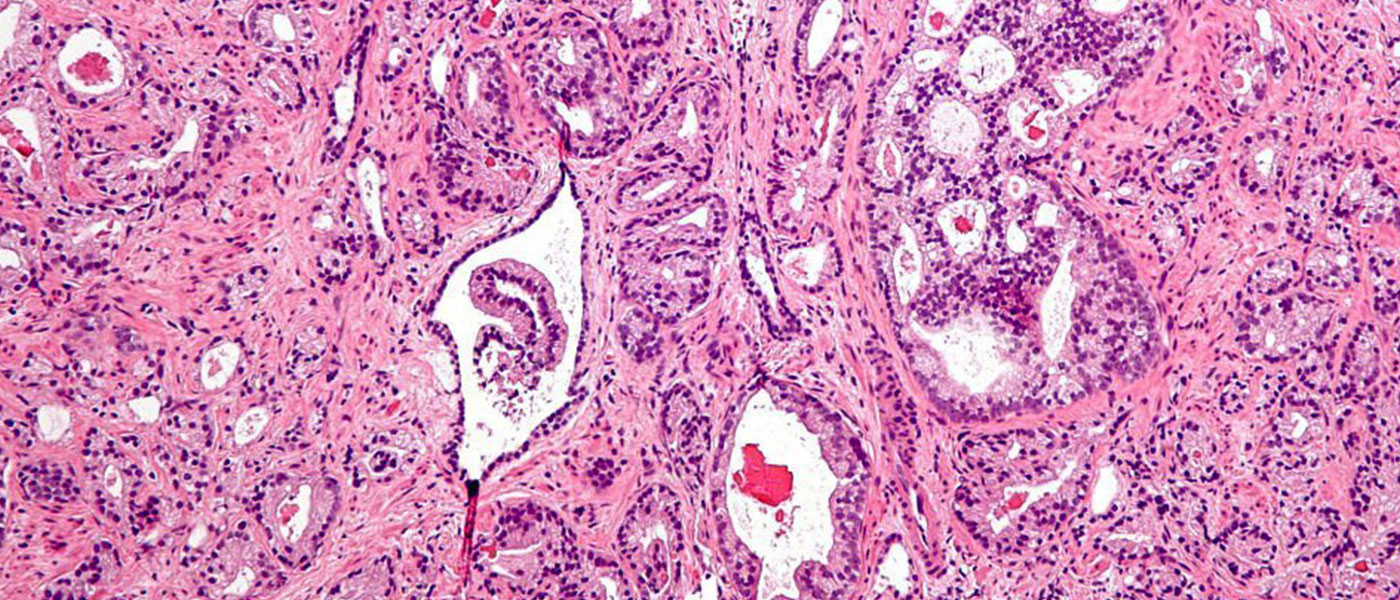

Prostate cancer is one of hardest cancers to diagnose and treat—but a recent discovery by scientists from various Russian institutions may help us develop a more targeted and effective way to manage it. Instead of fighting the cancer using drugs that ultimately damage the body’s healthy cells as it tries to kill the cancerous ones, 11 compounds have been identified that can lend itself to the development of more targeted and effective drugs.

The key to this discovery is based on the prostate specific membrane antigen (PSMA) proteins. Prostate cancer tissues apparently carry 10 times the level of PSMA proteins versus healthy tissues, making the cancer easy to spot.